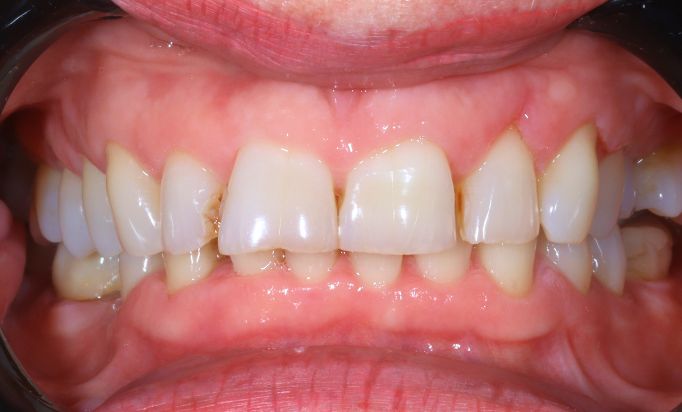

Cosmetic Dentistry

Improving smiles naturally

Helping you prevent dental issues with regular check-ups.